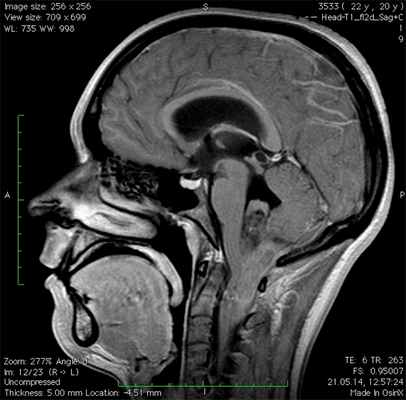

Обнаружить опухоль помогают методы диагностической визуализации. Основным методом визуализации, который обычно используется для оценки эпендимомы, является магнитно-резонансная томография (МРТ) головного и спинного мозга. Кроме того, МРТ проводится после хирургической операции, чтобы удостовериться, что опухоль удалена полностью.

Основная роль в диагностике субэпендимом принадлежит таким методам, как компьютерная томография и магнитно-резонансная томография. Эти методы схожи по своей сути и отличаются лишь технологией - в КТ применяется рентгеновское излучение, а в МРТ - мощное электромагнитное поле. Это довольно информативные методы визуализации опухолей мозга, которые позволяют определить локализацию опухоли, ее, размеры, форму и структуру.

Диагностика

Диагностика эпендимомы, как правило, начинается с осмотра у врача-невропатолога, который направляет пациента на обследования. При подозрении на опухоль головного мозга проводятся инструментальные методы диагностики – компьютерная томография (КТ), магнитно-резонансная томография (МРТ), для уточнения окончательного диагноза и определения объема новообразования, его локализации, наличия метастазов и других аспектов протекания болезни, важных при подборе методов лечения.